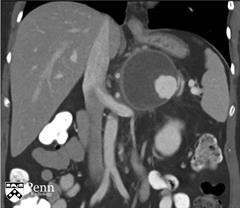

马女士, 55岁,左腰痛。腹部增强CT如下图所示。

于胰体/尾部的巨大的分叶状的囊性肿块,包绕脾动脉。其内可见一致密物在病变的内部下方与其分层。脾静脉内形成血栓,导致明显的胃肝和胃脾静脉曲张。见一假性动脉瘤起源于脾静脉的分支。

诊断:粘液性囊性肿瘤伴低度不典型增生,仅局限于胰腺,邻近慢性胰腺炎和假性囊肿形成伴囊内血栓。